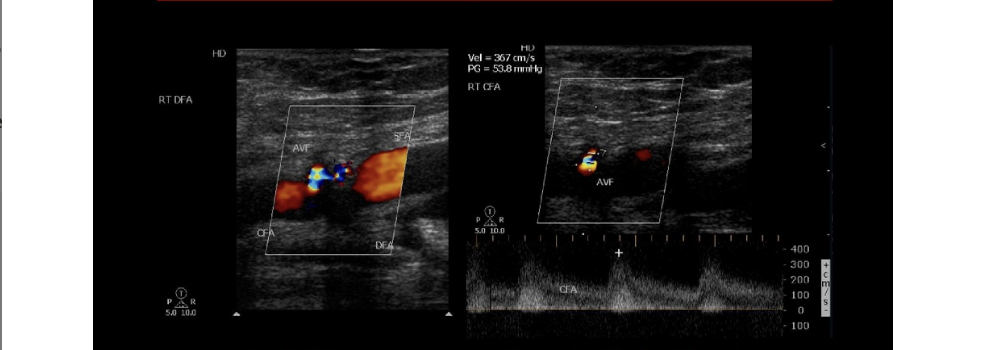

An AV fistula connects the femoral artery + vein at right groin. the doppler evaluation of the common femoral artery will show what pattern

.

a) biphasic flow w/increased diastolic flow

b) monophasic w/minimal diastolic flow

c) peak, triphasic waveform

d) monophasic w/increased diastolic